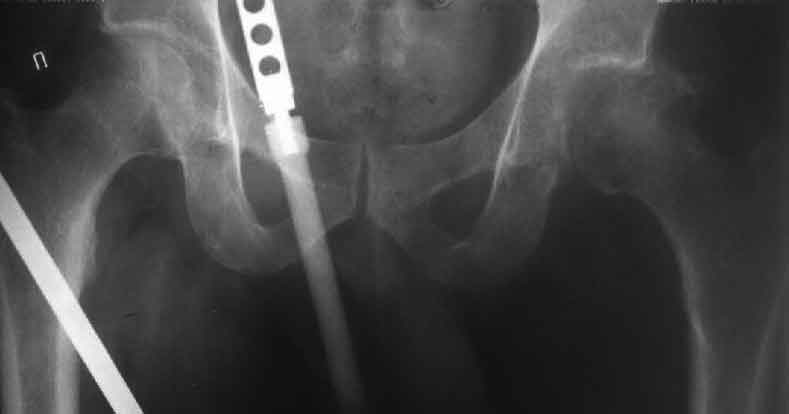

Еще пара фото, ситуация несколько иная, задачи те же, открытое вправление застарелого вывиха в 2002, молодой возраст. Сейчас госпитализирована для эндопротезирования.

Больного прооперировали на прошлой неделе (цементный протез, цемент с гентамицином). Использовали задне-боковой доступ. В области перелома подвижности практически не было, так что тему сообщения уместно заменить на "неправильно сросшаяся шейка". И в головке, и во впадине

были значительные дегенеративные изменения, так что ни биполяр, ни остеосинтез тут неуместны (хотя это предлагали в ortopod'е). После релиза удлинили ногу на 3 см. Дальше удлинять побоялись из-за

натяжения седалищного нерва, хотя в принципе можно было бы еще 15-20 мм нарастить. По послеоперационной рентгенограмме анатомическое укорочение порядка 15 мм. Клинически при ходьбе - 4 см, но это за счет перекоса таза.

The patient underwent cemented THR on last week. Postero-lateral approach was used. There was only minimal motion at the fracture site and we had to cut the femoral head with oscillating saw. The femoral head was deformed with it's cartilage completely absent in some areas.

Acetabulum showed gross degenerative changes, especially in superior rim. So I think it was right choice not to do ORIF in this case. After some soft tissue release we've lengthened the leg up to 3 cm. Further lengthening was possible but we stopped at that moment due to tension of n. ischiadicus. Now patient walks with crutches. Leg length discrepancy is about 4 cm due to pelvic tilt (discrepancy on post-op x-ray is 15 mm).